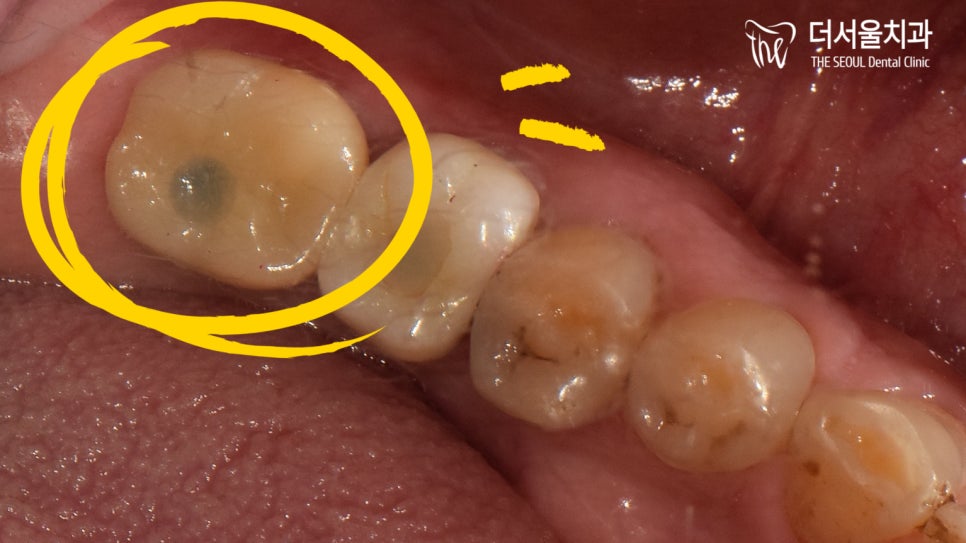

파노라마에서 확인해보니

아래 37번 치아 주변으로

골소실 및 염증이 나타나 있었습니다.

자세히 보면 치관 부위에

파절이 나타난 것으로 확인이 되는데요.

그로인해 염증이 발생하였고

오랜시간 방치를 하면서

병소가 점점 퍼지게 된 것입니다.